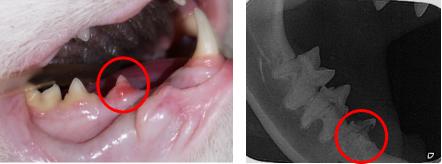

但是你看上面这个图,猫咪的一颗叫407的牙齿不见了!!! 而在绿色线圈里应该也还有一颗叫106的牙齿,也毫无踪迹。这是为什么呢? 因为这只猫咪患上了一种叫作牙吸收的疾病。 有研究显示,牙吸收在猫身上的发病率大概在28.5-67%,随着猫咪年龄的增长,出现牙吸收的概率也会增加。当它出现的时候,会发现 牙齿表面出现了粉色的肉芽组织 ,或者 牙龈增生包裹了牙齿 。 类似于像下图猫咪牙齿出现的问题。

左图:牙龈向牙冠爬行, 包裹 牙冠,牙龈炎

右图:X线发现牙齿呈“虫蚀”样